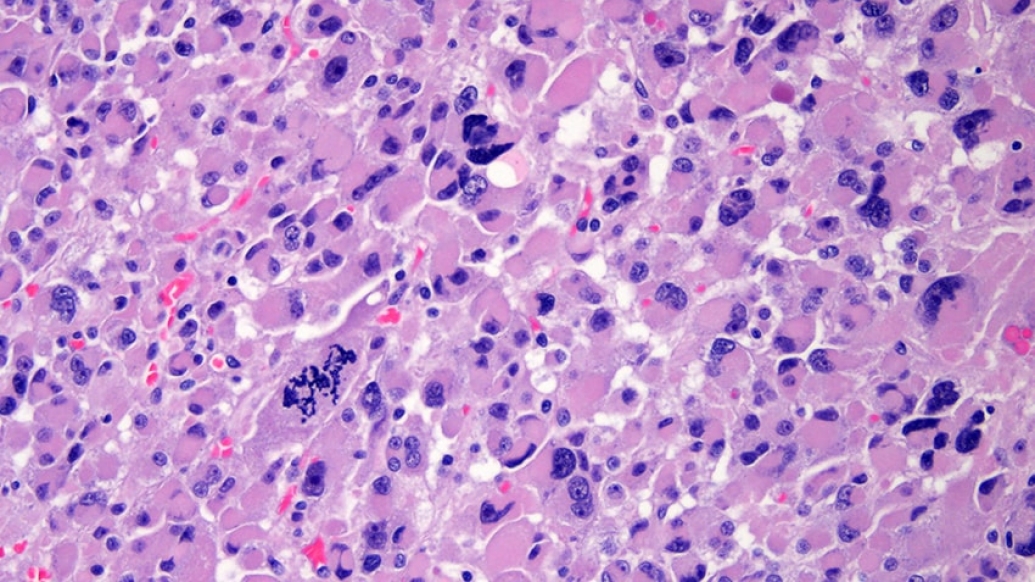

Teams from 39 institutions in Europe, North America, South America and Australia collected and analyzed 91 samples of adrenocortical carcinoma. They performed a comprehensive genomic analysis as part of The Cancer Genome Atlas Research Network.

The study revealed several interesting findings. One of the most exciting mutations is ZNRF3, which the researchers found to be lost in up to 20 percent of the adrenal cancers studied. The study also confirmed that mutations involved in benign adrenal disease play a role in adrenal cancer.

Researchers identified three distinct subtypes of adrenal cancer based on their molecular alterations. The subtypes were linked to different outcomes, suggesting a way to use molecular biomarkers to identify those patients likely to have more aggressive disease, and to more precisely match therapy with disease biology.